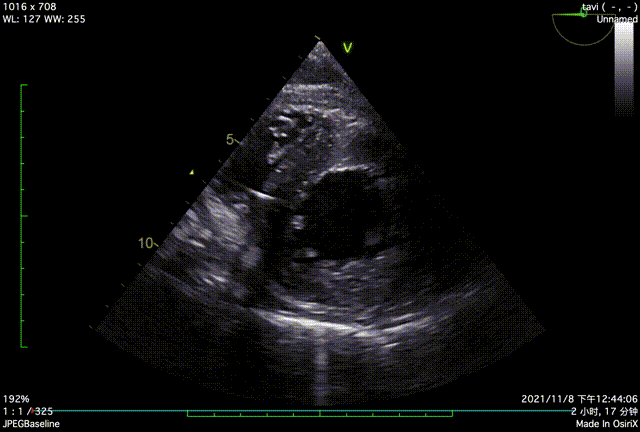

TTE入院

TTE